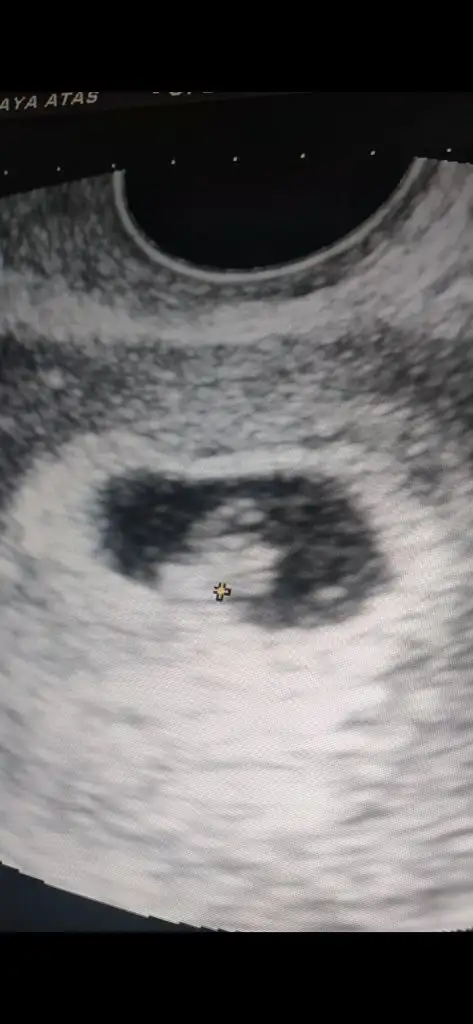

Maşallah canim allahim kucağına almayı nasip etsin darısı bana inşallah bende bi gitsem görsem sağlıklı ilerlediğini vallahi lakum dagitcamTeyzeleri bakin bebegim mucizem 7 haftalık oldu kalp seslerini de duydum bugün fasulye kadar

Maşallah maşallahhh minik fasülyeye sağlıcakla gelsinTeyzeleri bakin bebegim mucizem 7 haftalık oldu kalp seslerini de duydum bugün fasulye kadar